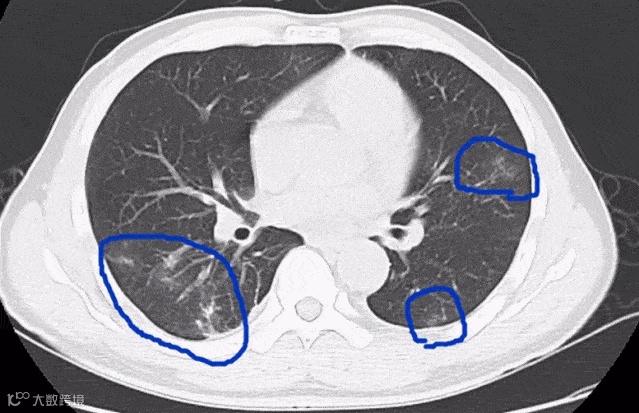

△寄生虫侵入肺部 图源/网络

像猪带绦虫、鱼绦虫、旋毛虫、弓形虫、囊虫和肺吸虫,它们都可能通过半生不熟的猪肉片、牛肉片和鱼、蟹等进入人体。

其中,某些寄生虫还会在人体内到处游荡,侵犯大脑、眼睛、躯干和四肢。